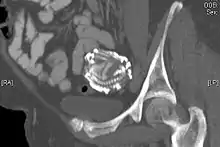

| Mrs. C (31) | London & Devon, Great Britain | Jan–June 1929 (presumed) | 1930-02-24 (seven months) |

"Skiagram confirmed...the fœtus was lying among coils of small intestine"[15] |

An 80-year-old woman presented in the outpatient department with severe abdominal pain. Ultrasound examination revealed a large echogenic mass (20 x 20 cm) in the right upper quadrant. An abdominal x-ray demonstrated the skeleton of a fully developed extrauterine fetus. It is presumed from the patient's history that this fetus was present for at least 40 years. Radiography revealed a fetus shrouded in a mantle of calcification. The fetus was hyper-flexed with other signs of "intrauterine" death. Fetal dentition charts dated the fetus at 34 weeks, the epiphyses being obscured by extensive calcification. In addition to subcutaneous calcification there was extensive visceral and intracranial calcification.[24] |